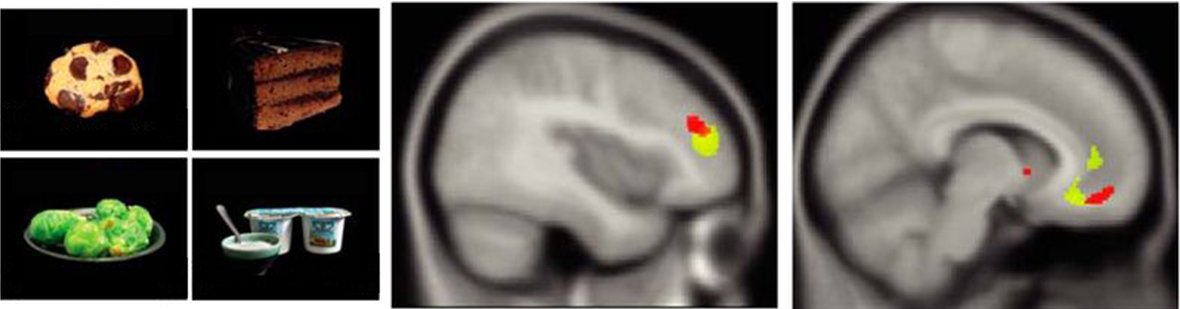

Will be speaking at

@ISMRM_ANZ tomorrow on the brain’s food choice network changes in obesity.https://twitter.com/ISMRM_ANZ/status/1200239982650126336 …

What will you have for a snack? A Journal Club by

@cassandra_lowe & @TheAmyR in#jneurosci@SfNJournals discusses work by@HPlassmann showing gray-matter differences linked to the ability to prioritize healthiness over tastiness when choosing foods. http://bit.ly/2B0WC1a pic.twitter.com/hduhonzRO4